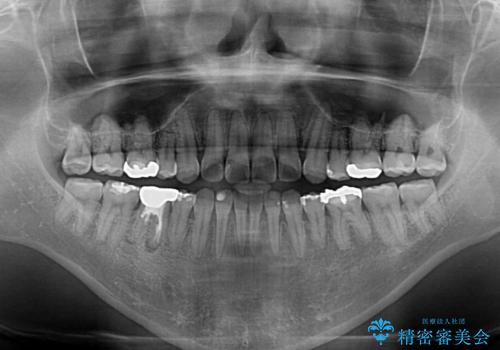

- 抜歯矯正の後戻りを気にして来院された患者様です。

舌の突出癖によるオープンバイトになり、前歯の叢生が後戻りしていました。

舌のトレーニングを行いながら、インビザラインを用いて矯正治療を行うこととしました。

インビザラインの特性を活用して奥歯の咬み合わせを圧下させることで、前歯のオープンバイトを改善さえることができました。